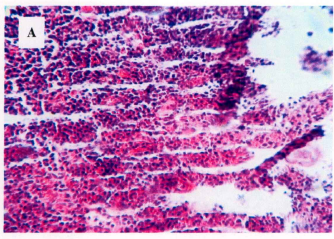

瘤组织经HE染色,光镜观察。有如下分析:肿瘤细胞体积较大,核大,核仁明显且多个,染色质粗细不一,多见核分裂,瘤内有片状坏死,坏死区内及周围有大量淋巴细胞浸润。

请问细胞核,核仁,染色质,淋巴细胞都在哪,该怎么看?

细胞核是苏木素的蓝色,细胞质是红色。

染色结果:胞核为苏木素染成鲜明红色,胞浆为伊红所染呈桃红色,其他如核仁、肌纤维、、胶原纤维等也为伊红所染,红细胞染成朱红色,染色好的切片应该是红蓝相映色彩鲜明。